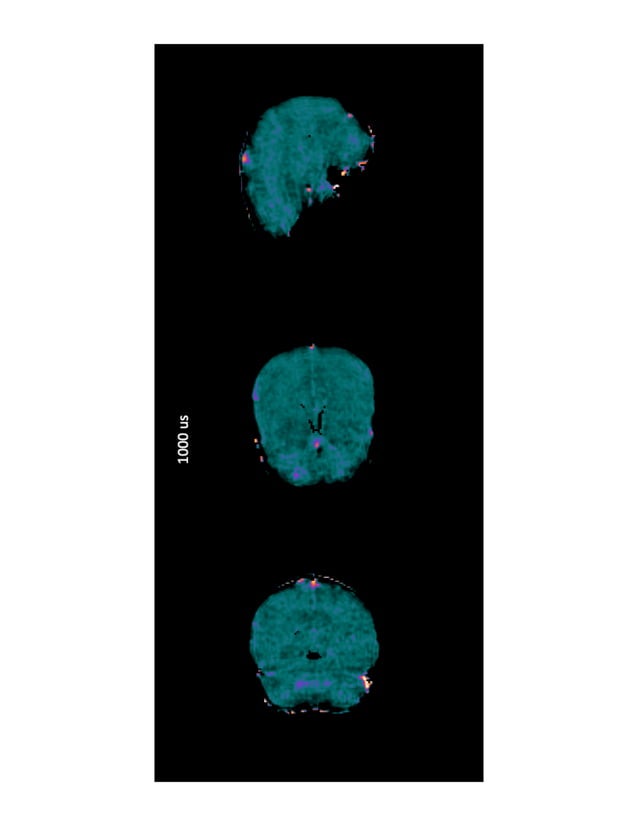

MR Images acquired using ultrashort echo time (UTE) sequence of

MR Images acquired using ultrashort echo time (UTE) sequence of Short Echo Time This review paper summarizes recent technical development in ultrashort echo time (ute) magnetic resonance imaging of. Tr and te are basic pulse sequence parameters and stand for repetition time and echo time respectively. This review article summarizes recent technical developments in ultrashort echo time (ute) magnetic resonance imaging of. The te used for clinical mrs ranges between 18 and 288ms.. Short Echo Time.